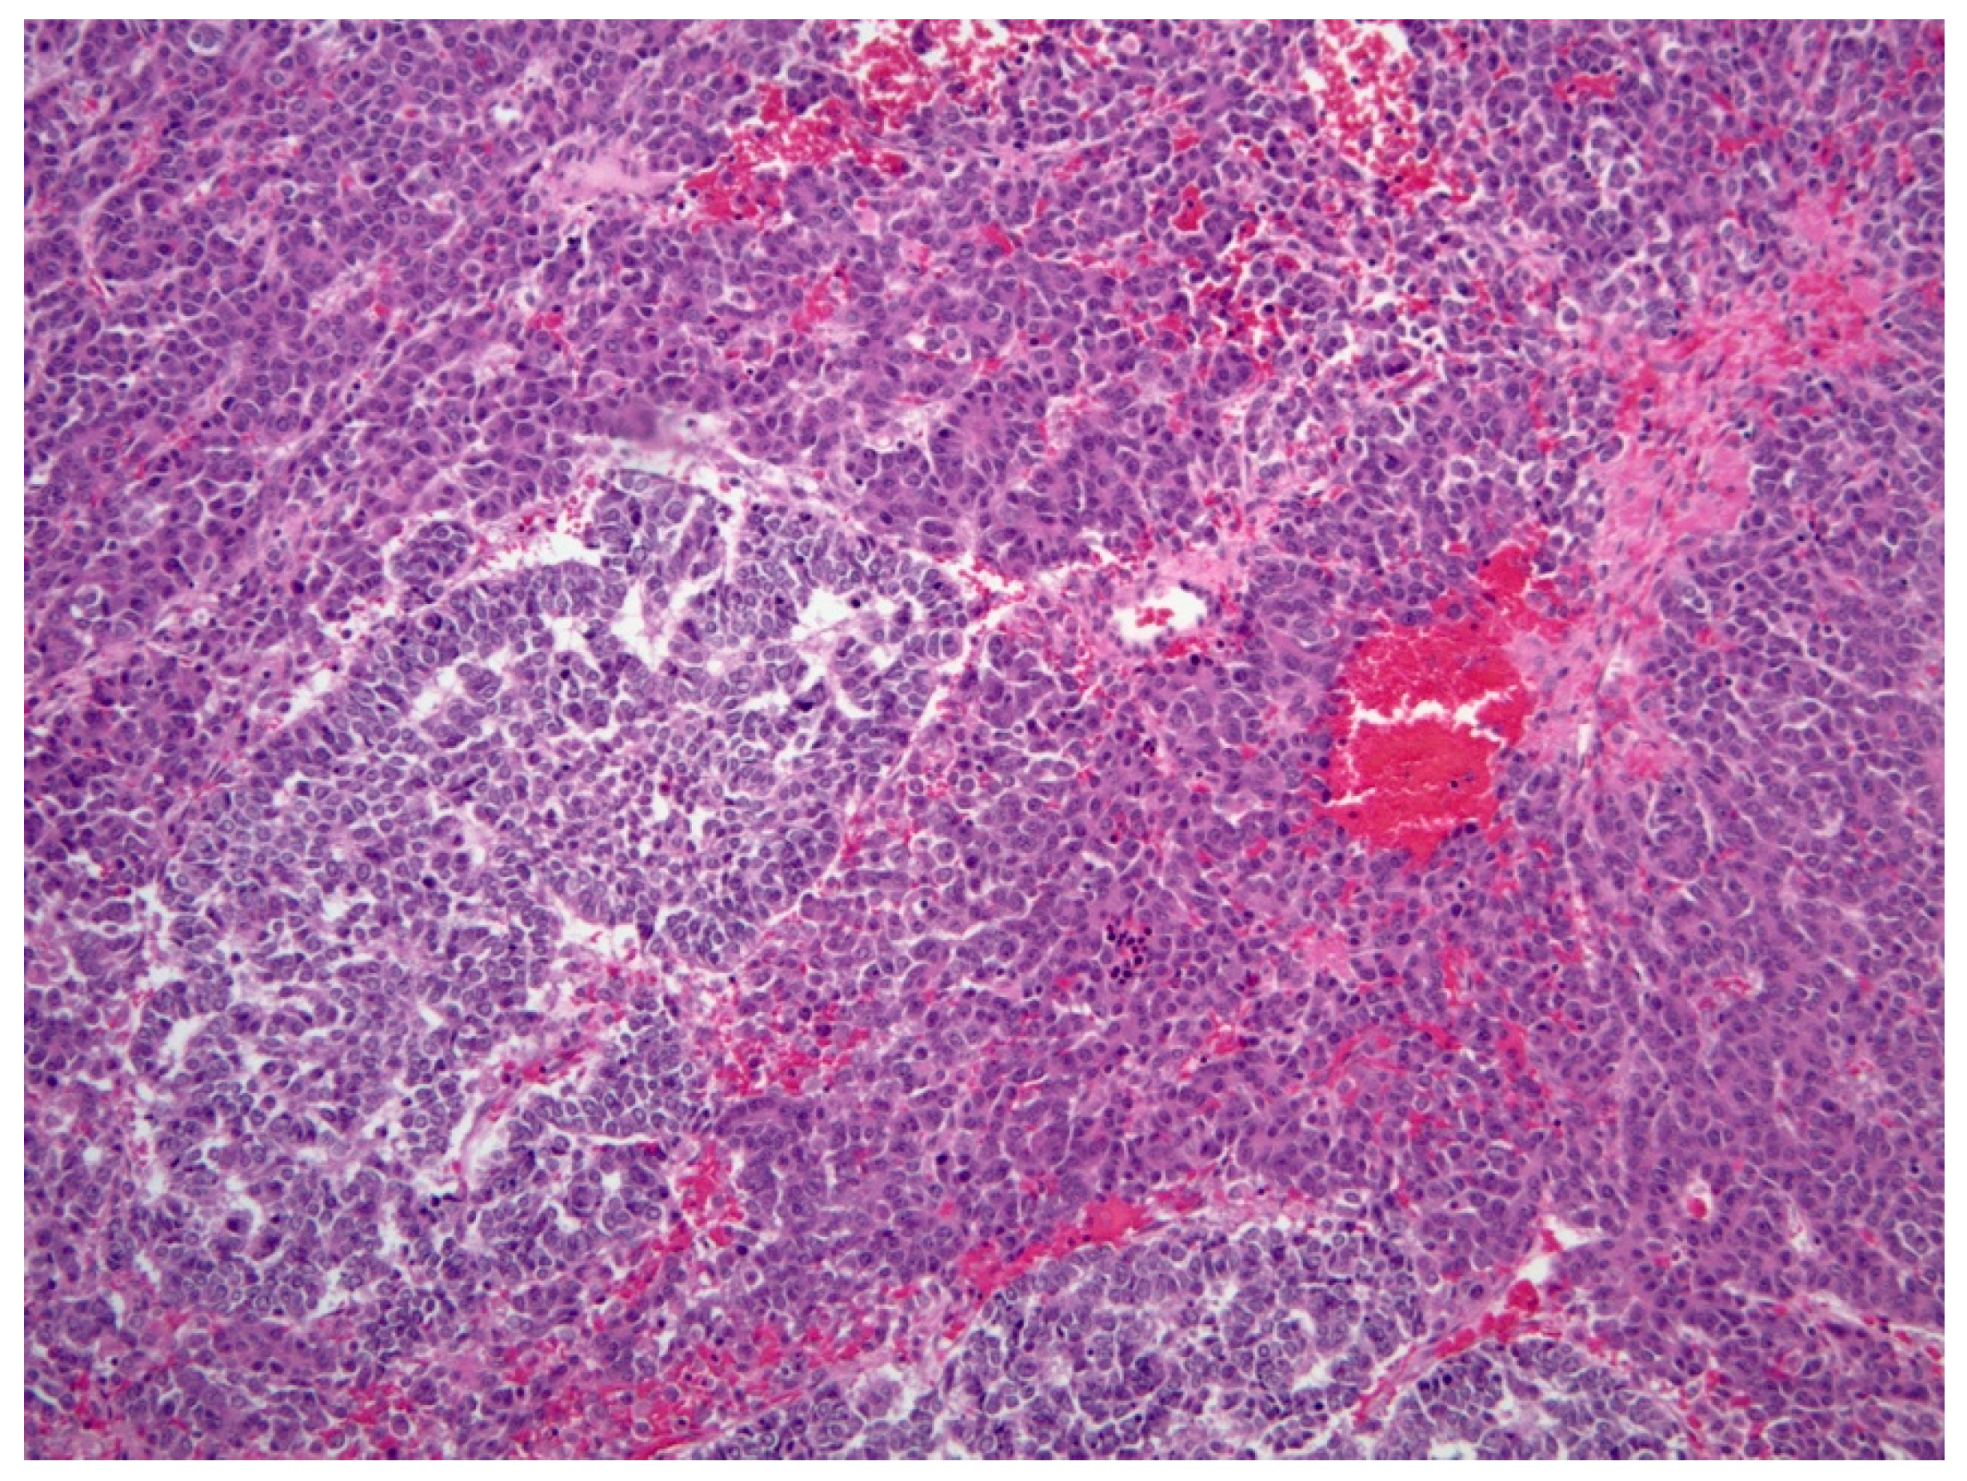

3.2.3. Histopathology